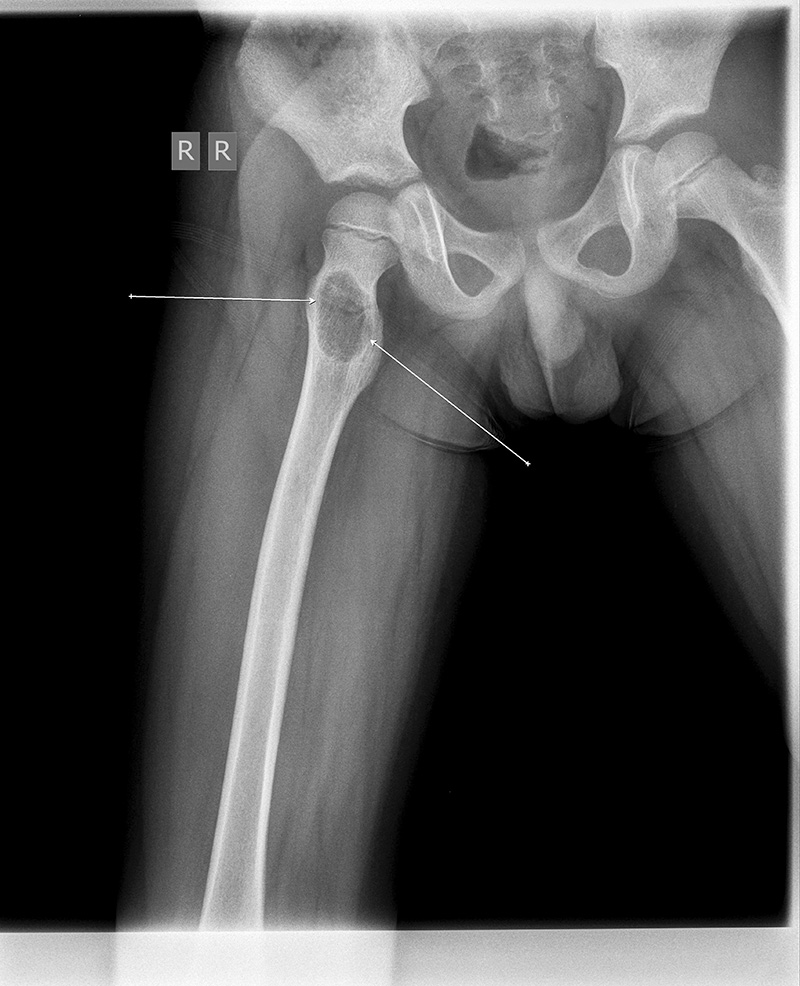

Рентгеновские снимки: Синовит тазобедренного сустава